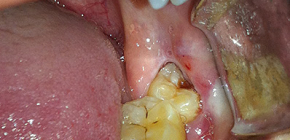

Spesso entro 1-3 giorni dopo l'estrazione del dente, i pazienti sviluppano vari gradi di gravità dell'edema dei tessuti molli che bordano il pozzo. L'edema più grave si osserva quando i molari vengono rimossi sulla mascella inferiore, ad esempio denti del giudizio retinati o semi-rinforzati, quando il viso può diventare in gran parte asimmetrico a causa del gonfiore dei tessuti. E questo è solo metà dei problemi - spesso un forte dolore e problemi con l'apertura della bocca si uniscono quando un pasto elementare trasforma una persona tormentata in vera tortura. È possibile inizialmente prevenire la comparsa di un edema pronunciato e cosa fare se tuttavia appare e acquisisce dimensioni impressionanti? In questi casi è possibile sviluppare complicazioni pericolose e quando dovrei correre dal medico per un aiuto il più presto possibile? Scopriamolo ...

Come se una persona non avesse paura di togliersi i denti, ma a volte devi comunque consultare un dentista per questo scopo. Le ragioni possono essere diverse e anche la complessità della procedura stessa può essere diversa: a volte tutto procede facilmente e rapidamente, letteralmente in 5 minuti, e a volte un medico può passare ore a mettere radici di un dente in piccoli pezzi da una gomma sanguinante lacerata.

Inoltre, in entrambi i casi, il paziente non è al sicuro da un'ampia varietà di complicazioni che possono insorgere sia direttamente durante la procedura di estrazione del dente sia dopo il suo completamento. Questi importantissimi problemi di salute saranno discussi in questa sezione del sito.